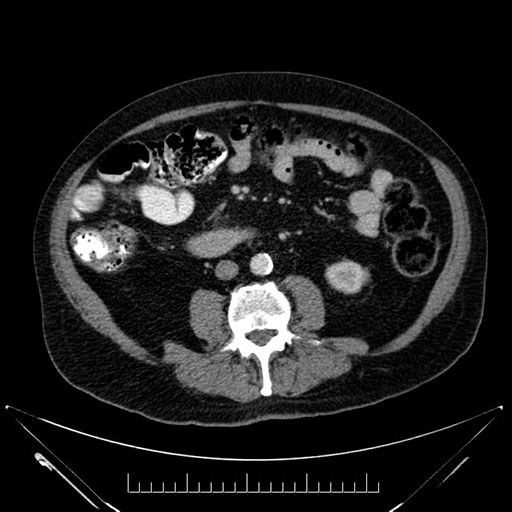

Coronal - stented